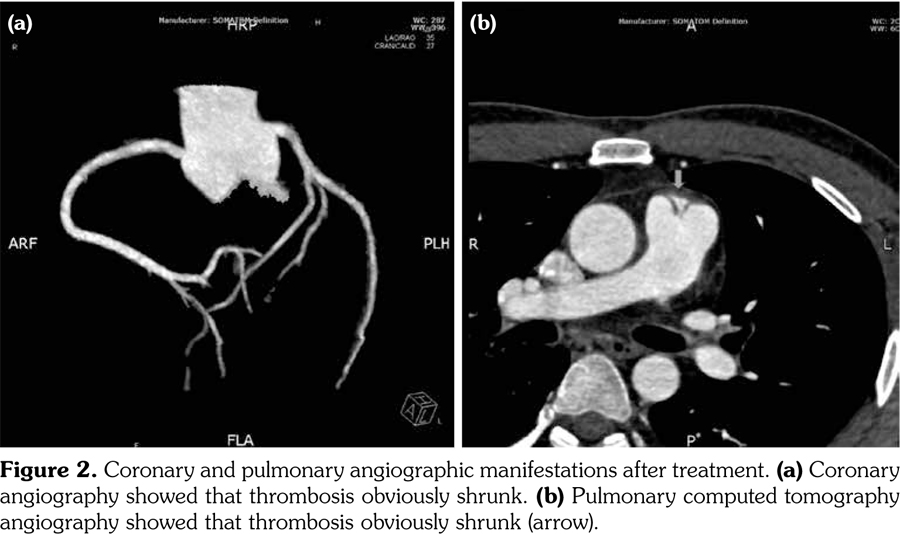

A 22-year-old male patient was admitted to our department in 2013. He had a history of recurrent erythema nodosum in lower limbs for over a two-year period. For the past one year, the patient complained of recurrent oral ulcer and arthralgia. For the past four months, he experienced low grade fever. In addition to fever, facial acneiform lesions were also noticed. Meanwhile, he also suffered chest pain which radiated to the left shoulder back. Physical examinations showed acne-like rashes over face and back, and erythema nodosum in limbs. Multiple minor ulcers were present on the buccal mucosa. Laboratory investigation revealed hemoglobin of 106 g/L, erythrocyte sedimentation rate of 120 mm/ hour, and C-reactive protein of 152 mg/L. Procalcitonin, myocardial enzymes, troponin I, antinuclear antibody and other autoantibodies were all negative. Bone marrow morphology showed poisoning changes. Electrocardiogram demonstrated lower ST segment on V2-V6 and T wave inversion on the V4-V6 lead. Then, the patient received coronary angiography that showed multiple coronary thrombi, and the stenosis reached about 90% (Figure 1a) at the root of the pulmonary artery. Pulmonary computed tomography angiography was also performed, which showed filling defects at the root of pulmonary main lobe arteries (Figure 1b). At the same time, positive pathergy test appeared on the site of bone marrow puncture. According to the International Criteria of BD(4) the patient was diagnosed as BD with oral ulcers, skin lesions, positive pathergy test and cardiovascular involvement. He was given immunosuppressive therapy, which covered oral prednisone 40 mg daily along with cyclophosphamide 500 mg every two weeks. After a two-month treatment, coronary angiography and pulmonary computed tomography angiography revealed that thrombi obviously shrunk (Figure 2). The dosage of prednisone and cyclophosphamide were tapered gradually. To date, the coronary and pulmonary artery thrombosis have regressed without recurrence for nearly four years. A written informed consent was obtained from the patient.